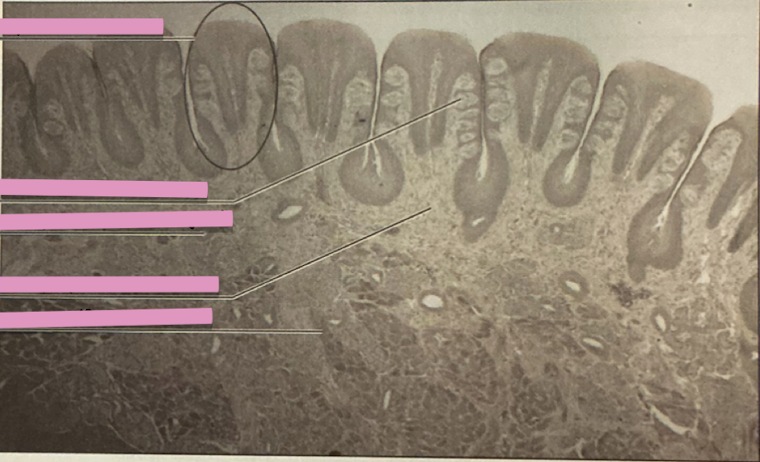

duodenum

brunner’s glands

intestinal epithelium

duodenum

________ receives chyme when stomach empties; exocrine release site for gallbladder & pancreatic secretions

intestinal glands

secrete mix of sucrase, maltase, & peptidases + definsins & enzymes

brunner’s glands

produce mucus-rich alkaline secretion to protect from acidic content, lubricate walls, & enable absorption

goblet cells

single-celled exocrine glands secrete mucus